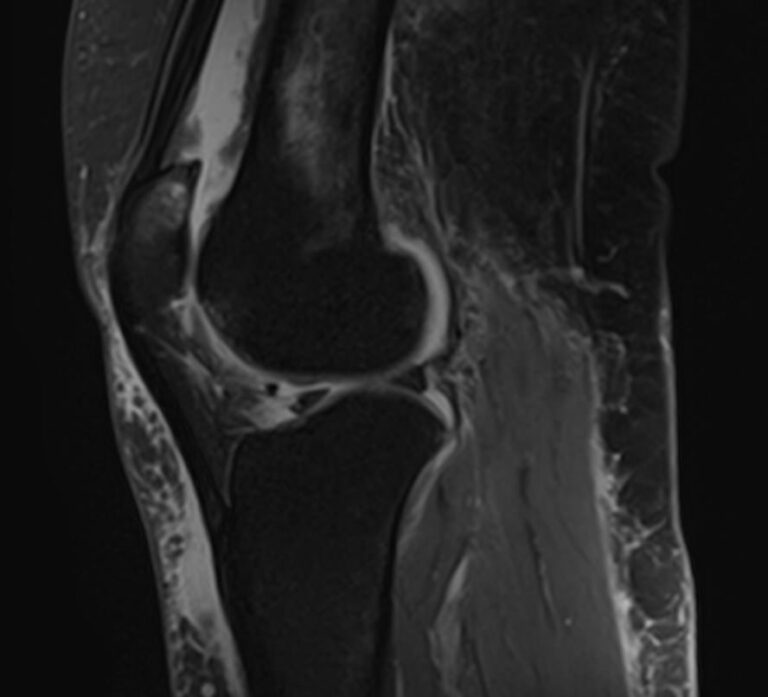

Магнитно-резонансная томография является высокоинформативным методом выявления причин возникновения заболеваний коленного сустава. В клинике «Доступная медицина» диагностика осуществляется на новейшем высокопольном томографе закрытого типа TOSHIBA VANTAGE TITAN 1,5 Тесла, обеспечивающем высочайшее качество изображений исследуемой зоны.

Томограф позволяет детально визуализировать как костные структуры колена, так и окружающие мягкие ткани данной анатомической области, включая мышцы, связки, нервные сплетение, сосуды.